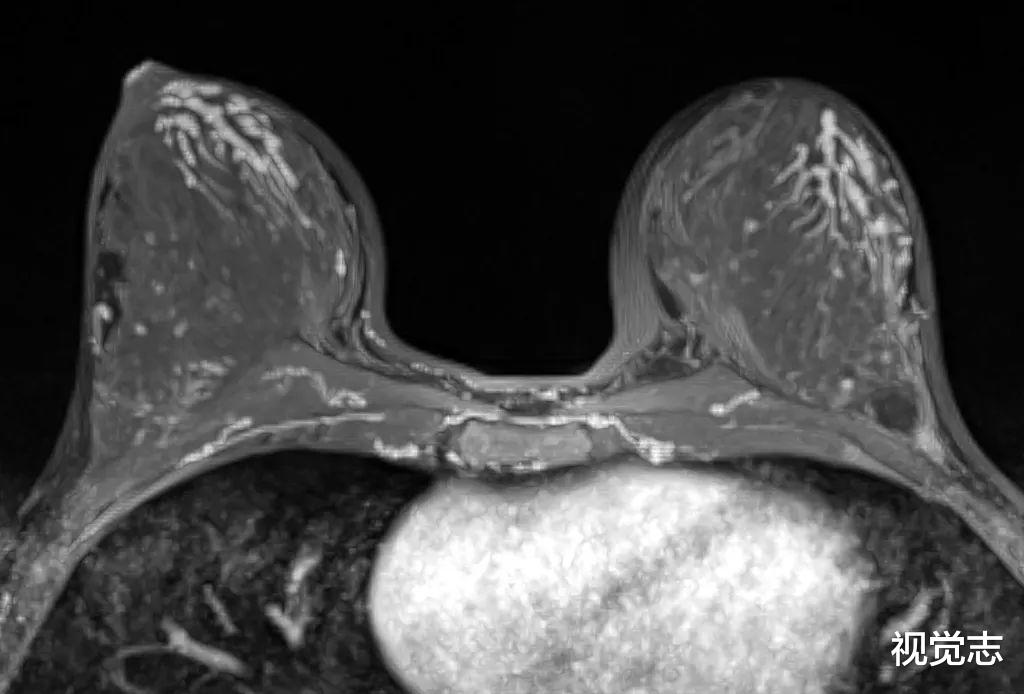

最近看到一则让人后背发凉的新闻——两年前 , 25岁的小丽体检查出甲状腺结节 , 医生叮嘱她要密切随访 。 但小丽害怕手术留疤 , 所以一拖再拖 。 再加上她发现身边好多同事都有结节的毛病 , 并且也都没去复查什么的 , 所以也就没太当回事儿 。 今年 , 小丽在体检时发现结节变大了 。 B超显示 , 结节大小1.2cm , 形态不规则 , 直立状 , 内见沙粒样钙化 , 可见短棒状血流 。 被确诊为甲状腺乳头状癌 。 万幸的是 , 小丽虽然被确诊为甲状腺癌 , 但是幸亏发现得早 , B超和CT都没有发现转移的淋巴结 , 可以通过腔镜进行根治性手术 , 治愈的可能性还是很高的 。

这样新闻看完让人不寒而栗 , 「结节」这二字在我们的的体检报告中是常见的 , 很多人看到之后都不当回事儿 , 把医生复查的叮嘱抛在脑后 。 事实上 , 身体释放的任何信号都不能大意 。 02一位网友分享了她从发现甲状腺结节 , 到确诊为甲状腺癌的经历 。 4月份 , 她在体检报告中发现了甲状腺结节 , 当时还没有发生钙化 。 4个月后 , 她再去三甲医院复查 , 报告显示边缘形状均不好 , 6个恶性指标 , 她的报告就占了4个 。 最后确诊为甲状腺癌 。